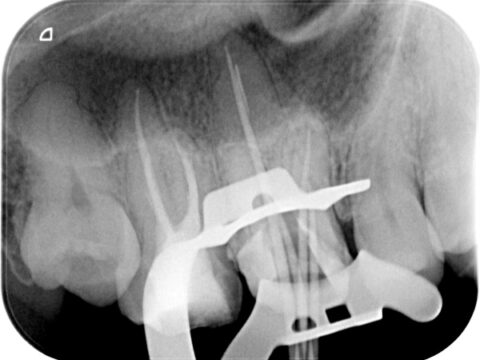

260226-001b